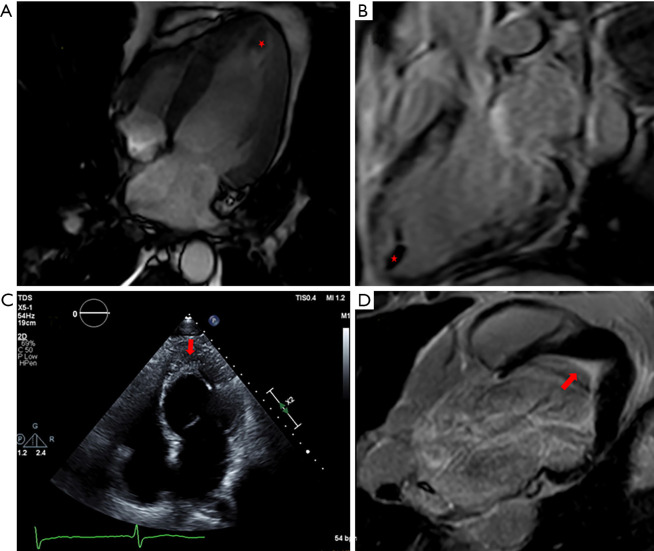

Results: Of 1,664 patients identified with hypereosinophilia (HE), 36 cases of clinically diagnosed HES were identified. Of the 36 patients diagnosed with HES, 11 patients (30.6%) were diagnosed with EM. Of these, six patients underwent endomyocardial biopsy (EMB). The mean age was 57±12 years and 63.6% were female. Asthma was the most common comorbidity (54.5%). Patients with EM had significantly more dyspnea (63.6%), fatigue (54.5%), and neuropathy (36.4%) compared to those without cardiac involvement. Echocardiography was performed in all patients and cardiac magnetic resonance (CMR) imaging was performed in eight patients. Left ventricular (LV) thrombus was detected more frequently by CMR (5/8, 62.5%) compared to echocardiography (3/10, 30%). Subendocardial pattern of late gadolinium enhancement (LGE) was observed in the majority of patients on CMR (6/7, 85.7%). Steroids were utilized in 90.9% of cases, and aspirin in all patients. Compared to HES patients without cardiac involvement, thromboembolic events occurred significantly more frequently (63.6% vs. 24.0%, P=0.02).

Conclusions: In a 37-year cohort of HES-associated EM, echocardiography was the first-line imaging modality, while CMR was an essential but still under-utilized imaging modality. Patients with EM had significantly more thromboembolic events compared to HES without cardiac involvement.